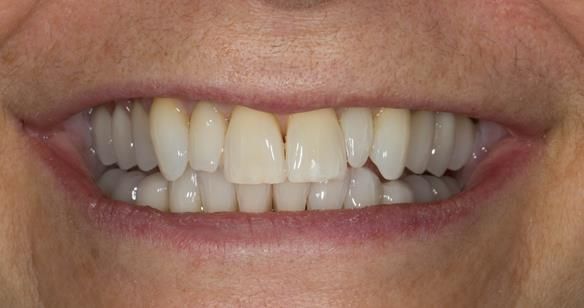

This newsletter describes in step by step detail Angela's transition through immediate partial dentures to crown supported definitive metal based dentures.

This 58 year old woman was referred to me by her general dental practitoner for treatment.

The clinical situation and treatment process is shown in detail below with photographs. I (Finlay Sutton) provided the clinical work and Rowan Garstang provided the technical work.